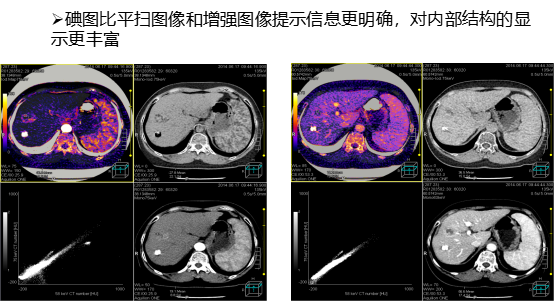

四、碘图及虚拟平扫图

碘图,直观反映脏器或组织的碘摄取情况即它的血供情况,对全器官或肿瘤的血流进行评估,可用于化疗效果的评估。

虚拟平扫图 ,减少扫描序列,可以用作常规CT平扫图像观察 ,减少病人辐射剂量 。